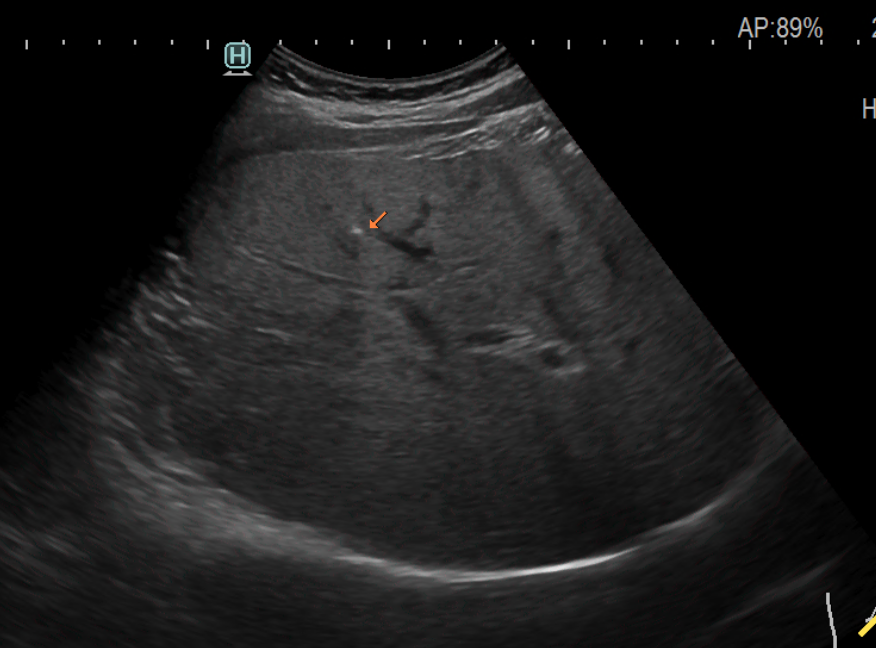

상복부 초음파 검사에서 종종 나오는 결과 중 하나가 간 석회화라는 소견입니다. 석회화라는 단어가 들어가서 마치 내 간이 딱딱하게 굳었거나 막혀있다고 잘못 이해하고 걱정하는 분들이 종종 있어서 그에 대해 간략하게 알아보겠습니다.

사실 석회화는 우리 몸에 존재하는 대부분의 장기에 다 생길 수 있습니다. 이렇게 석회화가 생기면 주변 조직보다 단단하고 딱딱해지기 때문에 초음파나 CT와 같은 영상 검사에서 주변 조직보다 새하얗게 보이게 됩니다.